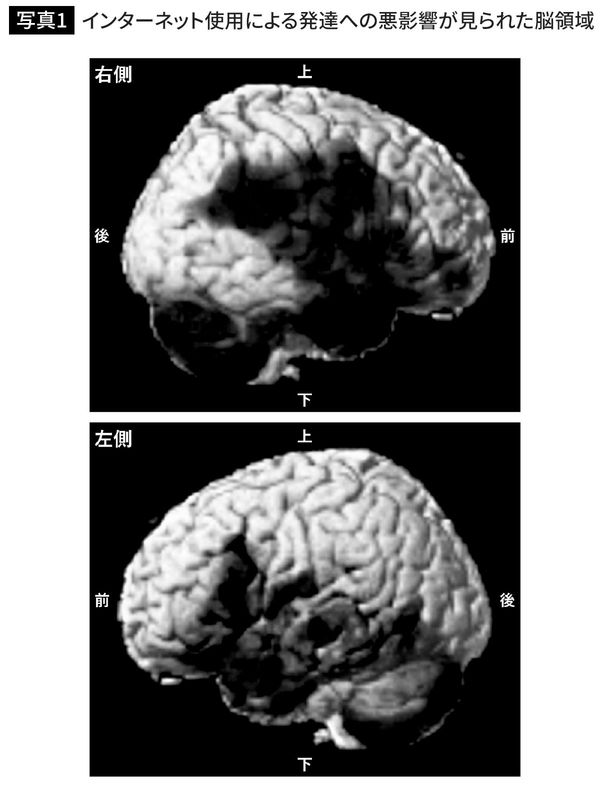

まず追跡前の時点で、子どもたちの脳の発達および、言語の能力には差がありませんでした。次に、追跡調査の結果【写真1】を見てみましょう。3年後に同じ計測を行なった結果、インターネットをたくさん使っていた子どもたちほど、3年間の言語能力の発達が小さく、幅広い範囲における脳の発達にも悪影響が見られました。黒い部分が、発達に悪影響が見られた脳の領域を表しています。幅広い範囲に色が塗られていることがわかります。

前頭前野や記憶や学習に関わる海馬に悪影響が出ていた

この写真は、脳の神経細胞の本体が集まっている灰白質の発達を表しています。神経線維が張り巡らされている白質についても、幅広い領域で発達への悪影響が見られました。これまで、同様の研究をテレビやゲームでも行なってきましたが、ここまで脳の広範囲における発達に悪影響が見られたのは初めてのことでした。

発達に悪影響が見られた脳領域には、認知機能を支える前頭前野、記憶や学習に関わる海馬のほか、言葉に関係する領域、感情や報酬を処理する領域などが含まれています。どれも私たちが生きる上で必要となる大切な機能です。